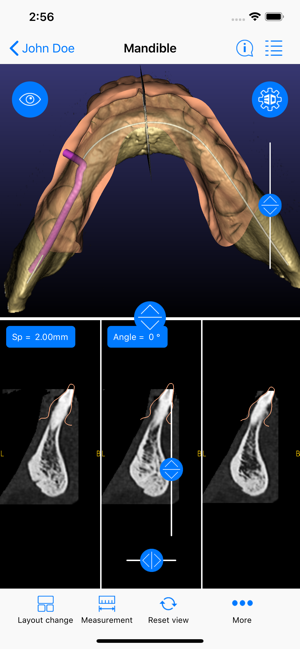

ICX-Magellan X is a cloud-based Software concept used for CBCT-Analysis and to create Implant-Treatment plans.

The ICX-Magellan X App completes this System primarily regarding communication, treatment-plans that were prepared at the pc can be shared with other users in real-time, commented, changed or confirmed.

The App can be integrated supporting any workflow; existing treatment-plans can be recalled, edited or used for patient-education anywhere anytime.